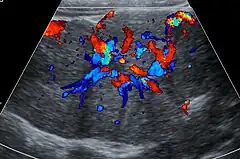

Unenhanced CT or MRI usually does not show the difference in intensity between the FNH and surrounding liver except when there is marked liver steatosis that reduces the attenuation of the liver, causing FNH to be hyperattenuating when compared with the surrounding liver. In the arterial phase CT or MRI, there is a strong enhancement not followed by washout. The lesion presents a slight hyperintensity or isodensity on portal venous phase or delayed phase images. There is also a presence of a central scar and absence of a capsule for the FNH.[5]